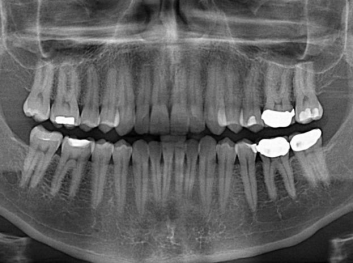

損壞的牙齒如何自我修復(fù)?近日,來自哈佛大學(xué)和諾丁漢大學(xué)的研究人員研發(fā)了能夠刺激牙齒干細(xì)胞再生的新型生物材料,而這種新材料研發(fā)成功的背后,正源于他們對牙齒如何實(shí)現(xiàn)自我修復(fù)這個(gè)課題的不斷探索。

據(jù)美國期刊《大眾科學(xué)(Popular Science)》報(bào)道,此種新型生物材料,不僅可以有效地取代傳統(tǒng)補(bǔ)牙填充物,刺激牙齒干細(xì)胞再生,患者也有望無需再接受根管治療,使蛀牙患者免除牙根感染或牙髓壞死的苦惱,一個(gè)全新的牙齒治療時(shí)代即將來臨。

Adam Celiz,是來自諾丁漢大學(xué)的研究人員,他和同事開發(fā)的這種新型合成生物材料,能刺激干細(xì)胞在牙髓部的生長。與普通材料一樣,這種合成材料被填充到牙齒并用UV光硬化。

在體外測試中,材料刺激干細(xì)胞進(jìn)入牙本質(zhì)的增殖和分化速度,促進(jìn)形成牙齒骨組織。研究人員認(rèn)為,一旦材料在受損牙齒中應(yīng)用,這些干細(xì)胞可以自動(dòng)修復(fù)來自填充物上的損壞。在本質(zhì)上,該生物材料將使牙齒自愈。

在未來,Adam Celiz說,可再生材料能制成各種填充物以便受損牙齒的自身治愈,降低補(bǔ)牙失敗率,甚至?xí)蟛糠秩藢Ω苤委煹男枰?/p>